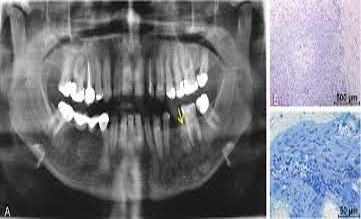

What does the radiograph show, indicating a potential need for root canal treatment?

What is the MOST likely treatment for this periapical lesion?

What is the MOST likely diagnosis based on the radiographic findings?